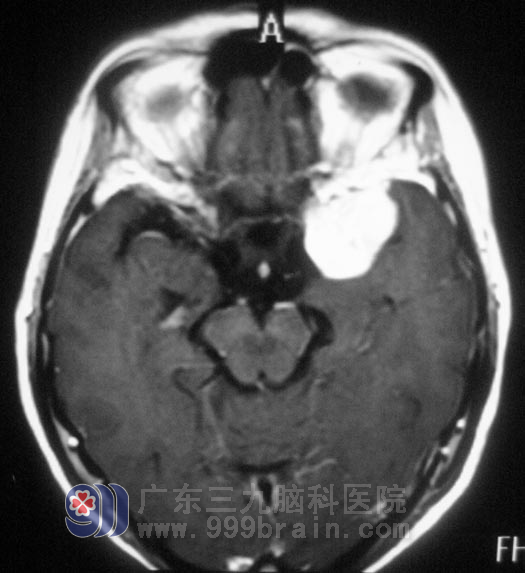

颈椎MR提示“颈4/5、5/6、6/7椎间盘突出”,头颅MR示“左侧蝶骨嵴脑膜瘤,大小约2.8cm×2.9cm×3.1cm”。家人回想起两年前,黄女士就开始出现左眼视力下降,偶有头晕,并没有引起重视,知道这个结果后肠子都悔青了。

11月23日,由广东三九脑科医院综合神经外科 鲁明主任主刀,在全麻下行左侧蝶骨嵴脑膜瘤切除术+颅内压探头植入术,术中取左侧额颞弧形切口,在显微镜下见肿瘤呈灰白色,与大脑中动脉粘连紧密,予肿瘤全切,对视神经、动眼神经保护完好。术后黄女士经过一段时间的恢复,诉左眼视力较术前明显好转,肩周炎也在广东三九脑科医院得到了有效的治疗。术后病理结果:过渡型脑膜瘤 WHO I 级。http://www.999brain.com/